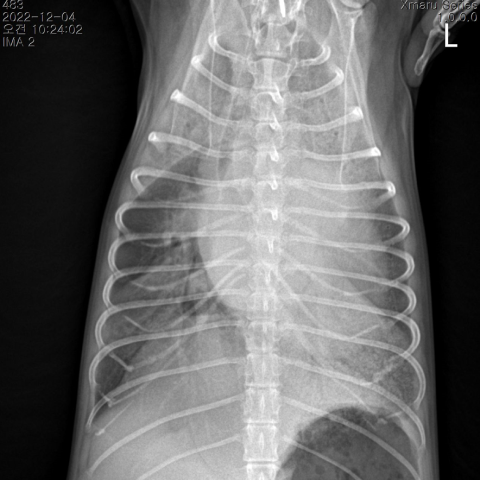

신체검사를 통해 심잡음이 청진 되면 ,흉부 방사선검사, 심장 초음파, BNP검사, 혈압검사를 실시 합니다. 이를 바탕으로 각 단계별 심장병 관리를 진행합니다.

울혈성 심부전

폐부종